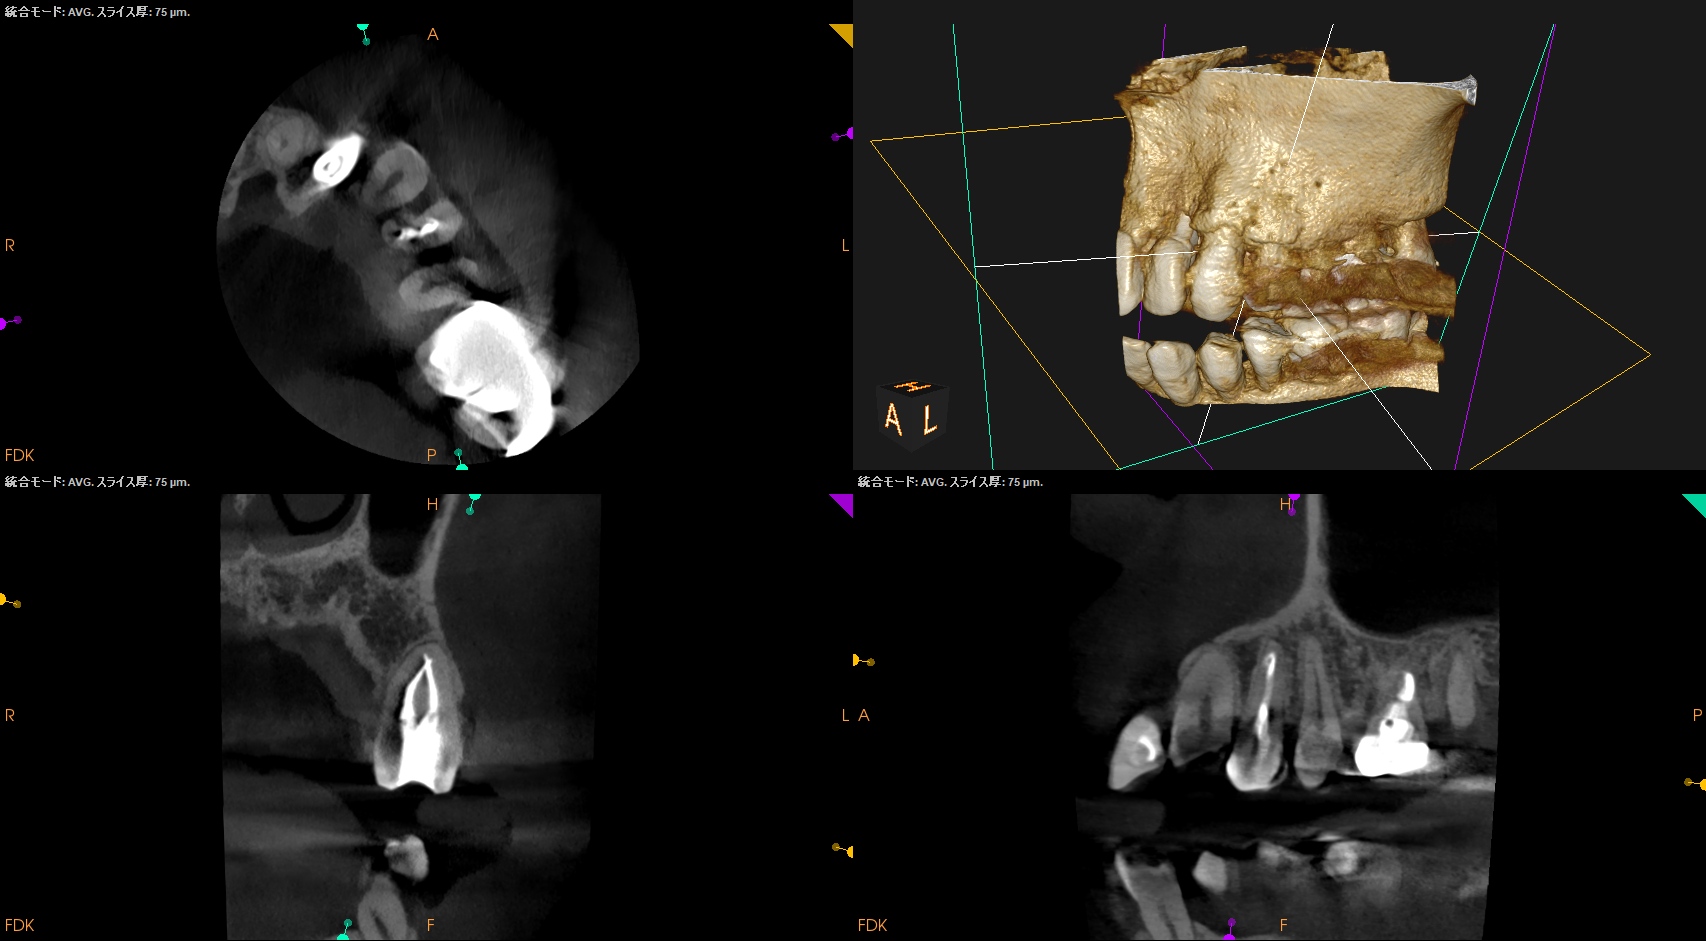

Pre-op Endo test(2026.1.6)

#11 Cold+1/2, Perc.(-), Palp.(-), BT(-), Perio probe(WNL), Mobility(WNL)

#12 Cold NR/20, Perc.(±), Palp.(-), BT(±), Perio probe(WNL), Mobility(WNL)

#13 Cold+2/2, Perc.(-), Palp.(-), BT(-), Perio probe(WNL), Mobility(WNL)

#12がCold testに反応しない。

この歯が怪しい。

PA(2026.1.6)

Inlay除去後のCR修復は適合がいいとは決していえない感じだ。

2根管性で非機能咬頭のBが直線根管だ。

直覆のような処置がなされた形跡がある。

成人での直覆の成功率は低いことがすでにわかっていることから臨床症状と相まって#12 RCTが主訴の解決に寄与する可能性が高いだろう。

Pre-op Endo Diagnosis(2026.1.6)

Pulp Dx: Pulp Necrosis

Periapical Dx: Normal apical tissues

Recommended Tx: RCT

また、治療前のCBCTで2根管性のことから合流部位の確認をいつものように行った。